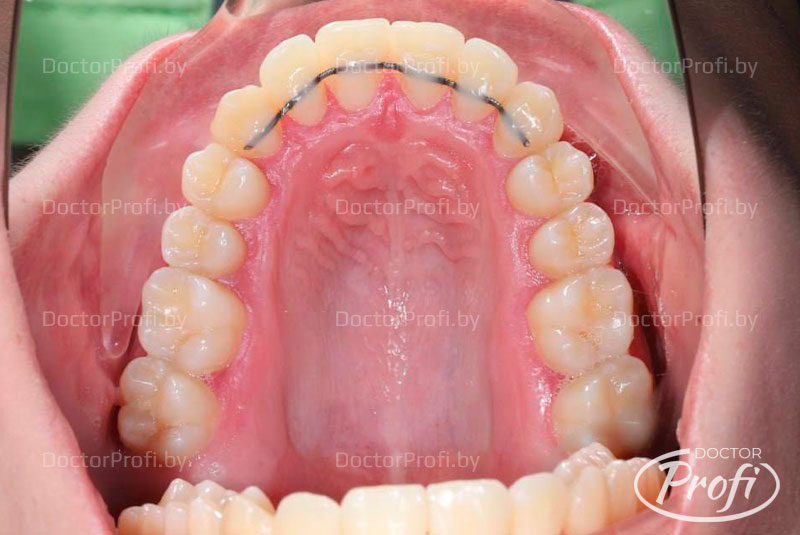

На основании полученных данных был установлен диагноз: двусторонний буккально-перекрестный прикус со смещением нижней челюсти вправо, дистальное соотношение зубов справа и тенденция к мезиальному прикусу слева; сужение и укорочение зубных дуг; скученное положение резцов на верхней и нижней челюсти с полным дефицитом места для зуба 22, а также истирание твердых тканей зуба 22 в пределах дентина; множественные ротации зубов и смещение центральной линии верхней челюсти влево на 3 мм.

Лечение проводила врач-ортодонт Дегтерева Илона Валерьевна с использованием самолигирующей брекет-системы Damon Q2 на обеих челюстях с избирательной пришлифовкой эмали на контактных поверхностях зубов во фронтальном отделе.

После снятия брекет-системы были установлены ретейнеры, а эстетическая реставрация зуба 22 была выполнена стоматологом-терапевтом высшей категории медицинского центра «Доктор Профи» Заблотской Екатериной Николаевной.